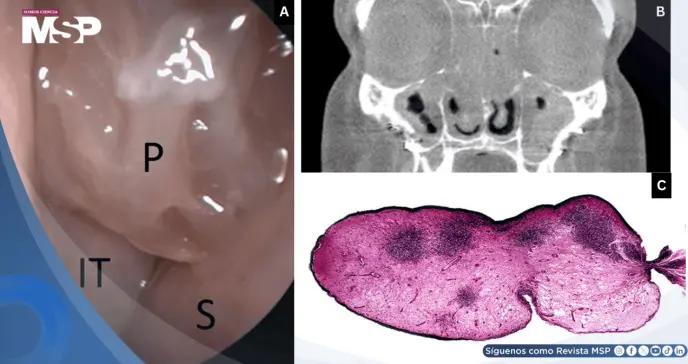

La rinoscopia anterior reveló hallazgos característicos: pólipos nasales de gran tamaño ocupando bilateralmente las cavidades nasales, cornetes inferiores hipertróficos y secreciones mucoides claras.

No se observaron costras ni cicatrices, lo cual ayudó a descartar diagnósticos diferenciales como la granulomatosis con poliangiitis.